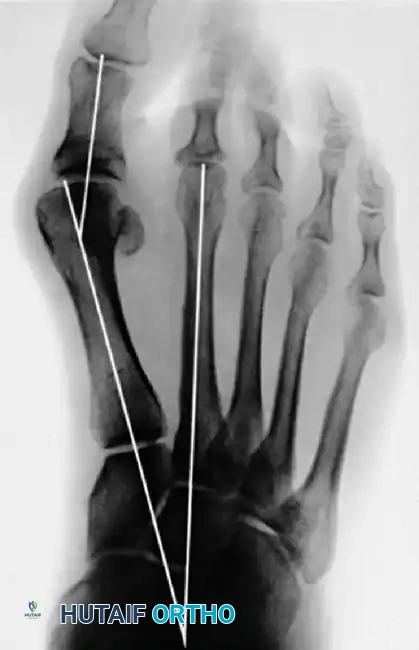

Figure 81-77: (A) Fixed hallux varus after a McBride bunionectomy. (B) Hallux varus after a McBride bunionectomy with fibular sesamoid excision. Removing the fibular sesamoid eliminates the valgus-producing moments of the adductor hallucis and the lateral head of the flexor hallucis brevis.

Figure 81-76: (A) Relatively mild hallux varus with symptomatic degenerative arthritis of the first metatarsophalangeal joint. (B and C) Arthrodesis was chosen as the definitive treatment due to the presence of advanced degenerative joint disease.